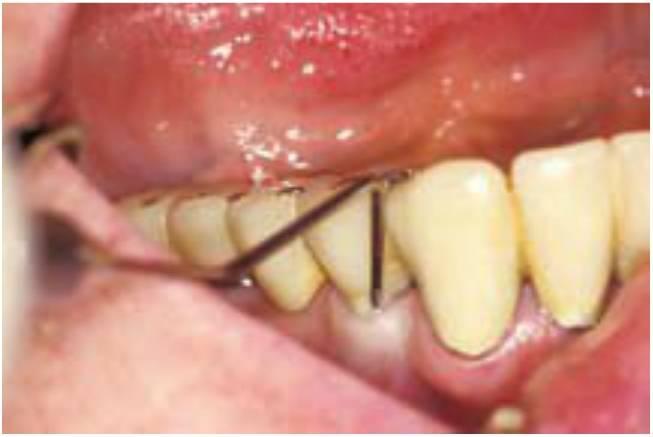

Una causa adicional del fracaso quirúrgico son los micromovimientos del implan te mientras se establece la interfase en desarrollo (fig. 4-3). Un brazo fracturado es inmovilizado para evitar movimiento en el foco de fractura para disminuir el riesgo de una falta de unión fibrosa. Se ha observado que movimientos tan pequeños como de 20 micrones pueden causar la formación de una interfase fibrosa en el foco de fractura. Brunski observó el desarrollo de una interfase de tejido fibroso cuando un implante dental se mueve más de 100 micrones durante la cicatrización inicial. El protocolo original Bránemark empleaba un enfoque quirúrgico de dos etapas. Uno de los principales motivos de este concepto era el de colocar el implante en la región de hueso de la cresta o por debajo de ella para disminuir el riesgo de movimiento del implante durante la cicatrización ósea inicial. Schroeder sugirió también un período de cicatrización sin cargas para los implantes, aunque el implante fuera colocado en los tejidos gingivales o ligeramente superior a estos.

Las fuerzas oclusales aplicadas sobre una prótesis removible sobre un implante en cicatrización pueden causar también la apertura de la línea de incisión de los tejidos blandos y retrasar la cicatrización de los mismos. Estas fuerzas oclusales pueden afectar también al hueso marginal alrededor del lecho implantológico en desarrollo. Transferir estas fuerzas a una prótesis mucosoportada situada por encima puede causar micromovimiento en la interfase implante-hueso, independientemente de que el implante esté cicatrizando por encima o por debajo de los tejidos gingivales. El estrés aplicado a un implante en fase de cicatrización aumenta el riesgo de complicaciones. Por otra parte, algunos informes clínicos multicéntricos indican que un cirujano experimentado puede obtener fijaciones rígidas tras una colocación quirúrgica en el 99 % de las ocasiones. El componente quirúrgico del fracaso implantológico suele representar el menor riesgo asociado con el tratamiento implantológico global.